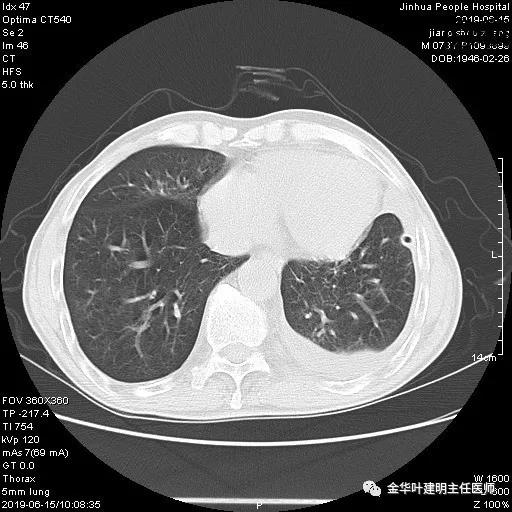

6.15上午:24小时胸管引流出血性液250ml;复查胸部CT示:

6.16上午:24小时引流量110毫升;

6.17上午:24小时引流量90毫升;